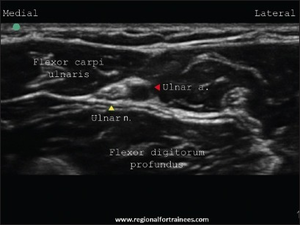

Ultrasound Guided Technique

- Have a partner help place the Linear Ultrasound Probe into the Sterile Probe Cover

- Starting mid forearm of the volar aspect in a transverse plane, locate the Ulnar Nerve

- Sliding Distally, the Ulnar Nerve and Artery should separate from each other

- Injection site is generally approximately 2 cm proximal to the wrist crease.

- In plane, visualize the needle on the Ultrasound monitor as you advance towards the Ulnar Nerve.

- Make sure to aspirate prior to injecting to rule out vascular penetration (low risk given ultrasound guidance)

- Discontinue and reposition should the patient report shooting "electrical" pains or numbness prior to injection

- Inject approximately 5 mL of local anesthetic in the area immediately surrounding the Ulnar Nerve